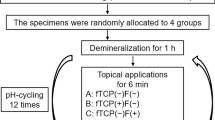

The crowns of each extracted sound tooth were removed. The remaining roots were divided into four parts (n = 12). Each sample was randomly allocated into one of four groups: Group 1 (Deionised water); Group 2 (BG with 540 ppm F); Group 3 (1,450 ppm F) and Group 4 (5,000 ppm F). ARCLs were developed using demineralisation solution (pH 4.8). The samples were then pH-cycled in 13 days using demineralisation solution (6 h) and remineralisation solution (pH 7) (16 h). Standard tooth brushing was carried out twice a day with the assigned toothpaste. X-ray Microtomography (XMT) was performed for each sample at baseline, following ARCL formation and after 13-day pH-cycling. Scanning Electron Microscope (SEM) and 19F Magic angle spinning nuclear magnetic resonance (19F-MAS-NMR) were also performed.

Three extracted sound teeth without dental caries, sealant, restorations or cracks were collected for the study from the Oral Surgery. Ethical approval was obtained prior to the study (QMREC 2011/99). Each tooth was stored in 0.1% thymol [18]. These teeth were then carefully cleaned and polished using non-fluoridated prophylaxis paste (NUPRO Dentsply, USA). The crowns of each tooth were removed 1 mm below the cemento-enamel junction by cutting the root surfaces using a 0.3 mm thick diamond disc under running water at 3,000 rpm speed (Struers, Copenhagen, Denmark) and divided into four sections in order to reduce any potential tooth to tooth variations. Subsequently, these four samples were allocated into each group (Table 1).

Formation of artificial root carious lesions

Lesions were formed in the 1.5 mmol/L CaCl2, 0.9 mmol/L KH2PO4, 50 mmol/L acetic acid and 1 M KOH adjusted to pH 4.8 for five days. In addition, 5.0 mmol/L NaN3 was added to the solution to prevent microbial growth. Each sample was separately placed in 10 ml of the solution with new solution changed every single day. During this period, these samples were kept in a 60 rpm shaking incubator (Staufen, Germany) at 37 °C. In the meantime, the procedure avoided any possible desiccation to prevent the shrinkage of ARCLs [19, 20]. .

The pH-cycling conditions

The rationale of the pH-cycling process was to simulate the dynamics between mineral loss and uptake as seen in the formation of dental caries [21]. This process contained exposure of dentine to alternate demineralisation and remineralisation cycles. The demineralisation solution composition was described in the preparation of artificial root carious lesions.

The remineralisation solution contained 1.5 mmol/L CaCl2, 0.9 mmol/L KH2PO4, 20 mmol/L HEPES and 130 mmol/L KCl. 5.0 mmol/L NaN3 was added to the solution to prevent microbial growth. The pH was adjusted to 7.0 using 1 M KOH. All chemical reagents were obtained from Sigma Aldrich, UK. Each sample was immersed in 10 mL of the demineralisation solution for six hours followed by immersion in 10mL of the remineralisation solution for 16 h. Fresh solutions were used for each cycle. This procedure was performed for a period of 13 days at 37 °C [20, 22].

The use of different toothpastes

A total of 12 samples with ARCLs were allocated into four different treatment groups. Each group (n = 3) received one of the allocated treatments (Table 1). Each toothpaste was diluted with deionised water at a dilution of 1:3 to make a toothpaste slurry. Tooth brushing was simulated using a medium-bristle toothbrush (Colgate Palmolive, UK) twice a day for 13 days. The brushing process was carried out using an electrically-powered tooth brushing machine (Boston Gear, Braintree, MA) designed to produce constant reciprocal movements with 150 g force for 10 s [23]. The samples were left for two minutes prior to rinsing with deionised water [24].